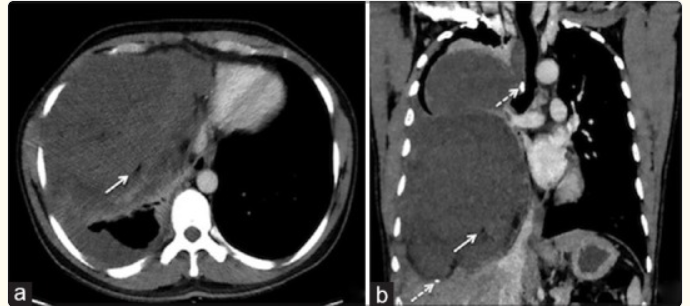

Aspectos macroscópicos do tumor fibroso. A massa está aderida à pleura visceral por um pedículo (seta sólida branca) e apresenta: Aspecto nodular em redemoinho (whorled) Focos de necrose ao corte Em relação à pleura adjacente: Ângulos obtusos com a pleura (seta sólida preta) são característicos Entretanto, lesões volumosas podem formar ângulos agudos com a pleura (seta curva preta) na imagem seccional (TC/RM)

Imagem composta com TC contrastada (CECT) nos planos axial (à esquerda) e coronal (à direita) de um homem de 66 anos com tumor fibroso localizado benigno demonstra uma massa de partes moles na fissura maior direita. Observa-se morfologia em “bico” (beak-like) do tumor ao longo da fissura interlobar adjacente (seta sólida em ciano), achado que sugere origem pleural/fissural da lesão.